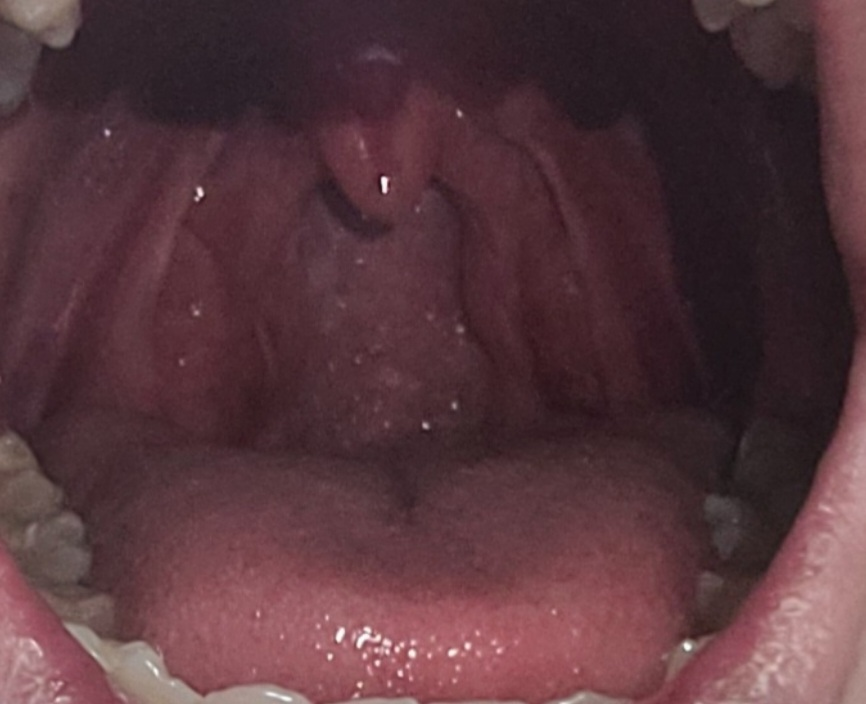

편도가 일반보다는 크면 제거하는 편이 좋나요?

편도가 평균사이즈보다 큽니다

그래서 그런지몰라도 목이 자주건조하고 칼칼해지는 경우가 많은데 편도 큰편이면 제거하는 편이 좋나요?

만성 편도염이 자주 발생하는 경우, 편도 비대를 동반할 수 있지만 현재 정도의 크기는

경도의 비대로 수술이나 치료가 필요한 정도는 아닙니다. 편도염이 일년에 3번 이상 반복

되는 경우는 수술적 제거를 고려할 수 있습니다.

편도는 임파선이 풍부한 신체 기관으로 비대한 경우 수술로 제거하기도 하지만 제거후에도 편도염이 발생할 수는 있습니다.